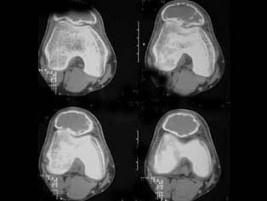

问题 患者,男性,30岁,近2年来感右膝疼痛,活动后加重,2周前由于剧烈运动后,右膝活动受限,右膝压痛明显,有波动感,皮肤稍显红肿,以髌骨部明显,请结合所提供图像,选择最佳选项 ( )

选项 A、骨巨细胞瘤 B、动脉瘤样骨囊肿 C、非骨化性纤维瘤 D、骨囊肿 E、纤维性骨皮质缺损

答案 B